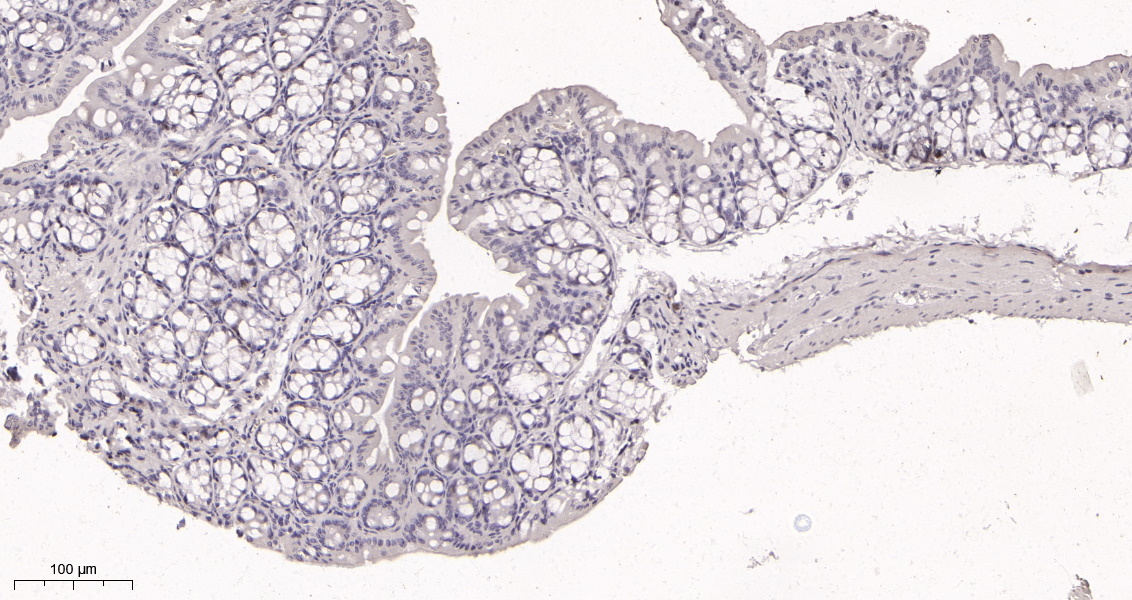

货号IM68914

产品名称Ki67 (16S9) Rabbit Monoclonal Antibody

推荐应用WB,IHC-P,IF-P,IF-F,IF-ICC,ELISA

稀释度IHC-P 1:200-1000,WB 1:1000-5000,IF-P/IF-F/IF-ICC 1:200-1000,ELISA 1:5000-20000,IP 1:50-200

背景介绍This gene encodes a nuclear protein that is associated with and may be necessary for cellular proliferation. Alternatively spliced transcript variants have been described. A related pseudogene exists on chromosome X. [provided by RefSeq, Mar 2009],

功能developmental stage:Expression of this antigen occurs preferentially during late G1, S, G2 and M phases of the cell cycle, while in cells in G0 phase the antigen cannot be detected.,function:Thought to be required for maintaining cell proliferation.,online information:Ki-67 entry,similarity:Contains 1 FHA domain.,subcellular location:Predominantly localized in the G1 phase in the perinucleolar region, in the later phases it is also detected throughout the nuclear interior, being predominantly localized in the nuclear matrix. In mitosis, it is present on all chromosomes.,subunit:Interacts with KIF15. Binds through the FHA domain to MKI67IP.,